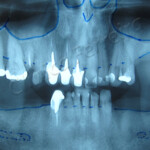

Implantes dentários são suportes ou estruturas de metal posicionadas cirurgicamente no osso maxilar abaixo da gengiva. Uma vez colocados, permitem ao dentista montar dentes substitutos sobre eles.

Implantes ósseo integrado: estes são implantados cirurgicamente diretamente no osso maxilar. Uma vez cicatrizada a região da gengiva que o circunda, uma segunda cirurgia é necessária para conectar um pino ao implante original. Finalmente, um dente artificial (ou dentes) é conectado ao pino, individualmente, ou agrupado em uma prótese fixa ou dentadura.

Implantes subperiósticos: consistem numa estrutura metálica que é encaixada sobre o maxilar bem abaixo do tecido da gengiva. Assim que a gengiva cicatriza, a armação torna-se fixa ao maxilar. Pinos, que são ligados à armação, projetam-se através da gengiva. Assim como no implante ósseo integrado, dentes artificiais são, então, encaixados nos pinos.